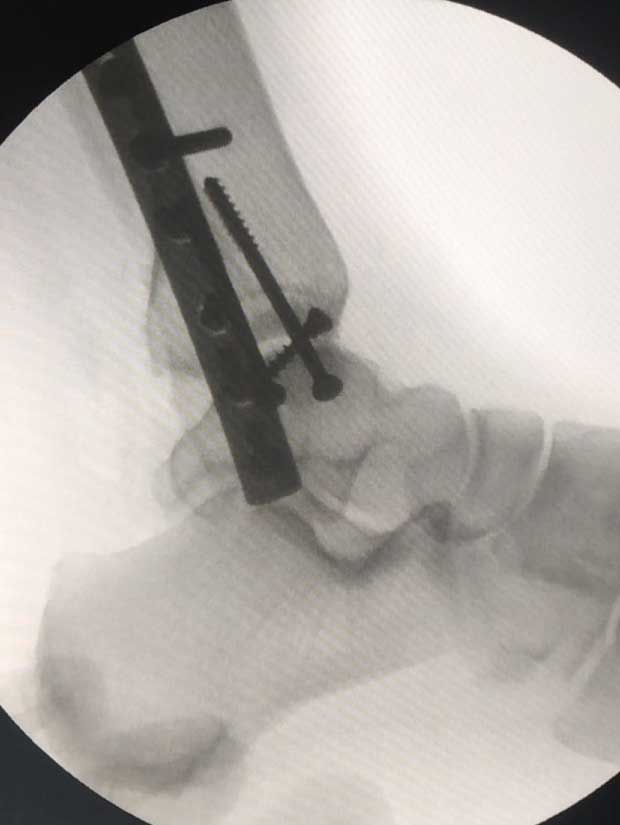

Caso No. 10 - Luxofractura de tobillo

Posoperación

Diagnóstico: Luxofractura de tobillo

Tratamiento: Cirugía: reducción abierta y fijación interna